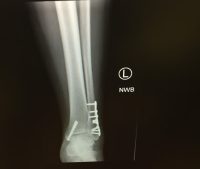

Because of the fall, Meg was immediately transported by ambulance to a local hospital. Her foot was turned outward in an unnatural position. She was in severe pain and was diagnosed with a trimalleoler fracture – which is a 3-bone fracture to the lower leg that forms the ankle joint. The bones are the medial malleolus (bone on the inside of the ankle), the lateral malleolus (bone on the outside of the ankle) and the posterior malleolus (bone on the tibia). Meg required surgery consisting of a plate and screws. After surgery she was unable to walk on her leg for six weeks, then had to use a CAM boot and knee scooter for months. She endured many sessions of physical therapy to help strengthen the ankle and at least give her some range of motion back.